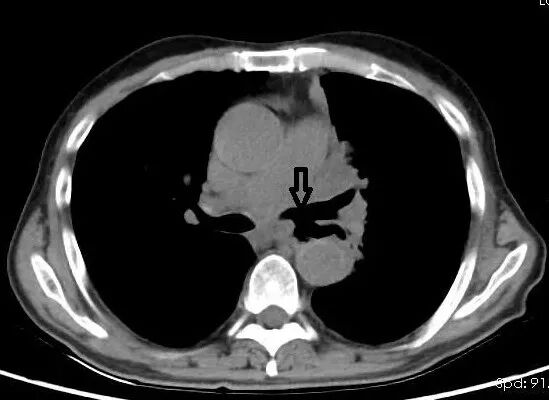

正某(化名)是一位晚期肺癌患者,于本次入院前1周出现了饮水呛咳、咳嗽、咳黄痰、发热等症状。考虑到正某存在肺部肿瘤病史,住院后我们为他进行了胸部CT的检查。检查结果发现病人肺部肿瘤侵犯肺门部纵隔淋巴结,可见看到明显的食管-气管相连,经过判定,考虑出现了食管-气管瘘的情况。